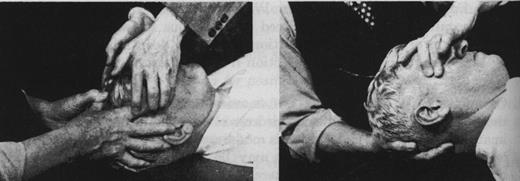

Рис.11.3. Подход со стороны свода к сфенобазилярному симфизу.

Рис.11.4 Лобнозатылочный подход к сфенобазилярному симфизу.

Кисть одной руки чашеобразно расположена под затылочной чешуей медиальнее латеральных углов. I и II пальцы другой руки на больших крыльях основной кости, ладонь - на чешуе лобной кости. Ни в коем случае не сдавливайте медиально крылья основной кости кончиками пальцев!

Флексия возникает при приведении лобной области в вентрокаудальное положение и затылочной кости в вентрокраниальное положение посредством вращения основной и затылочной костей вокруг их фронтальных осей. Вращение затылочной кости не является обязательным. Бывает достаточно лишь одного движения основной кости.